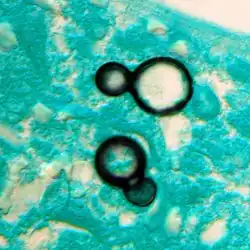

Granuloma with early suppuration. The fungal organisms are difficult to recognize at this low magnification. -

Large yeast-like fungi seen within giant cells at arrows. -

Large yeast-like fungi seen within giant cells at arrows. Budding yeasts in the cytoplasm of giant cells at the arrows. Broad-based budding and double-contoured cell walls are seen in the giant cell in the center are characteristic of Blastomyces dermatitidis. -